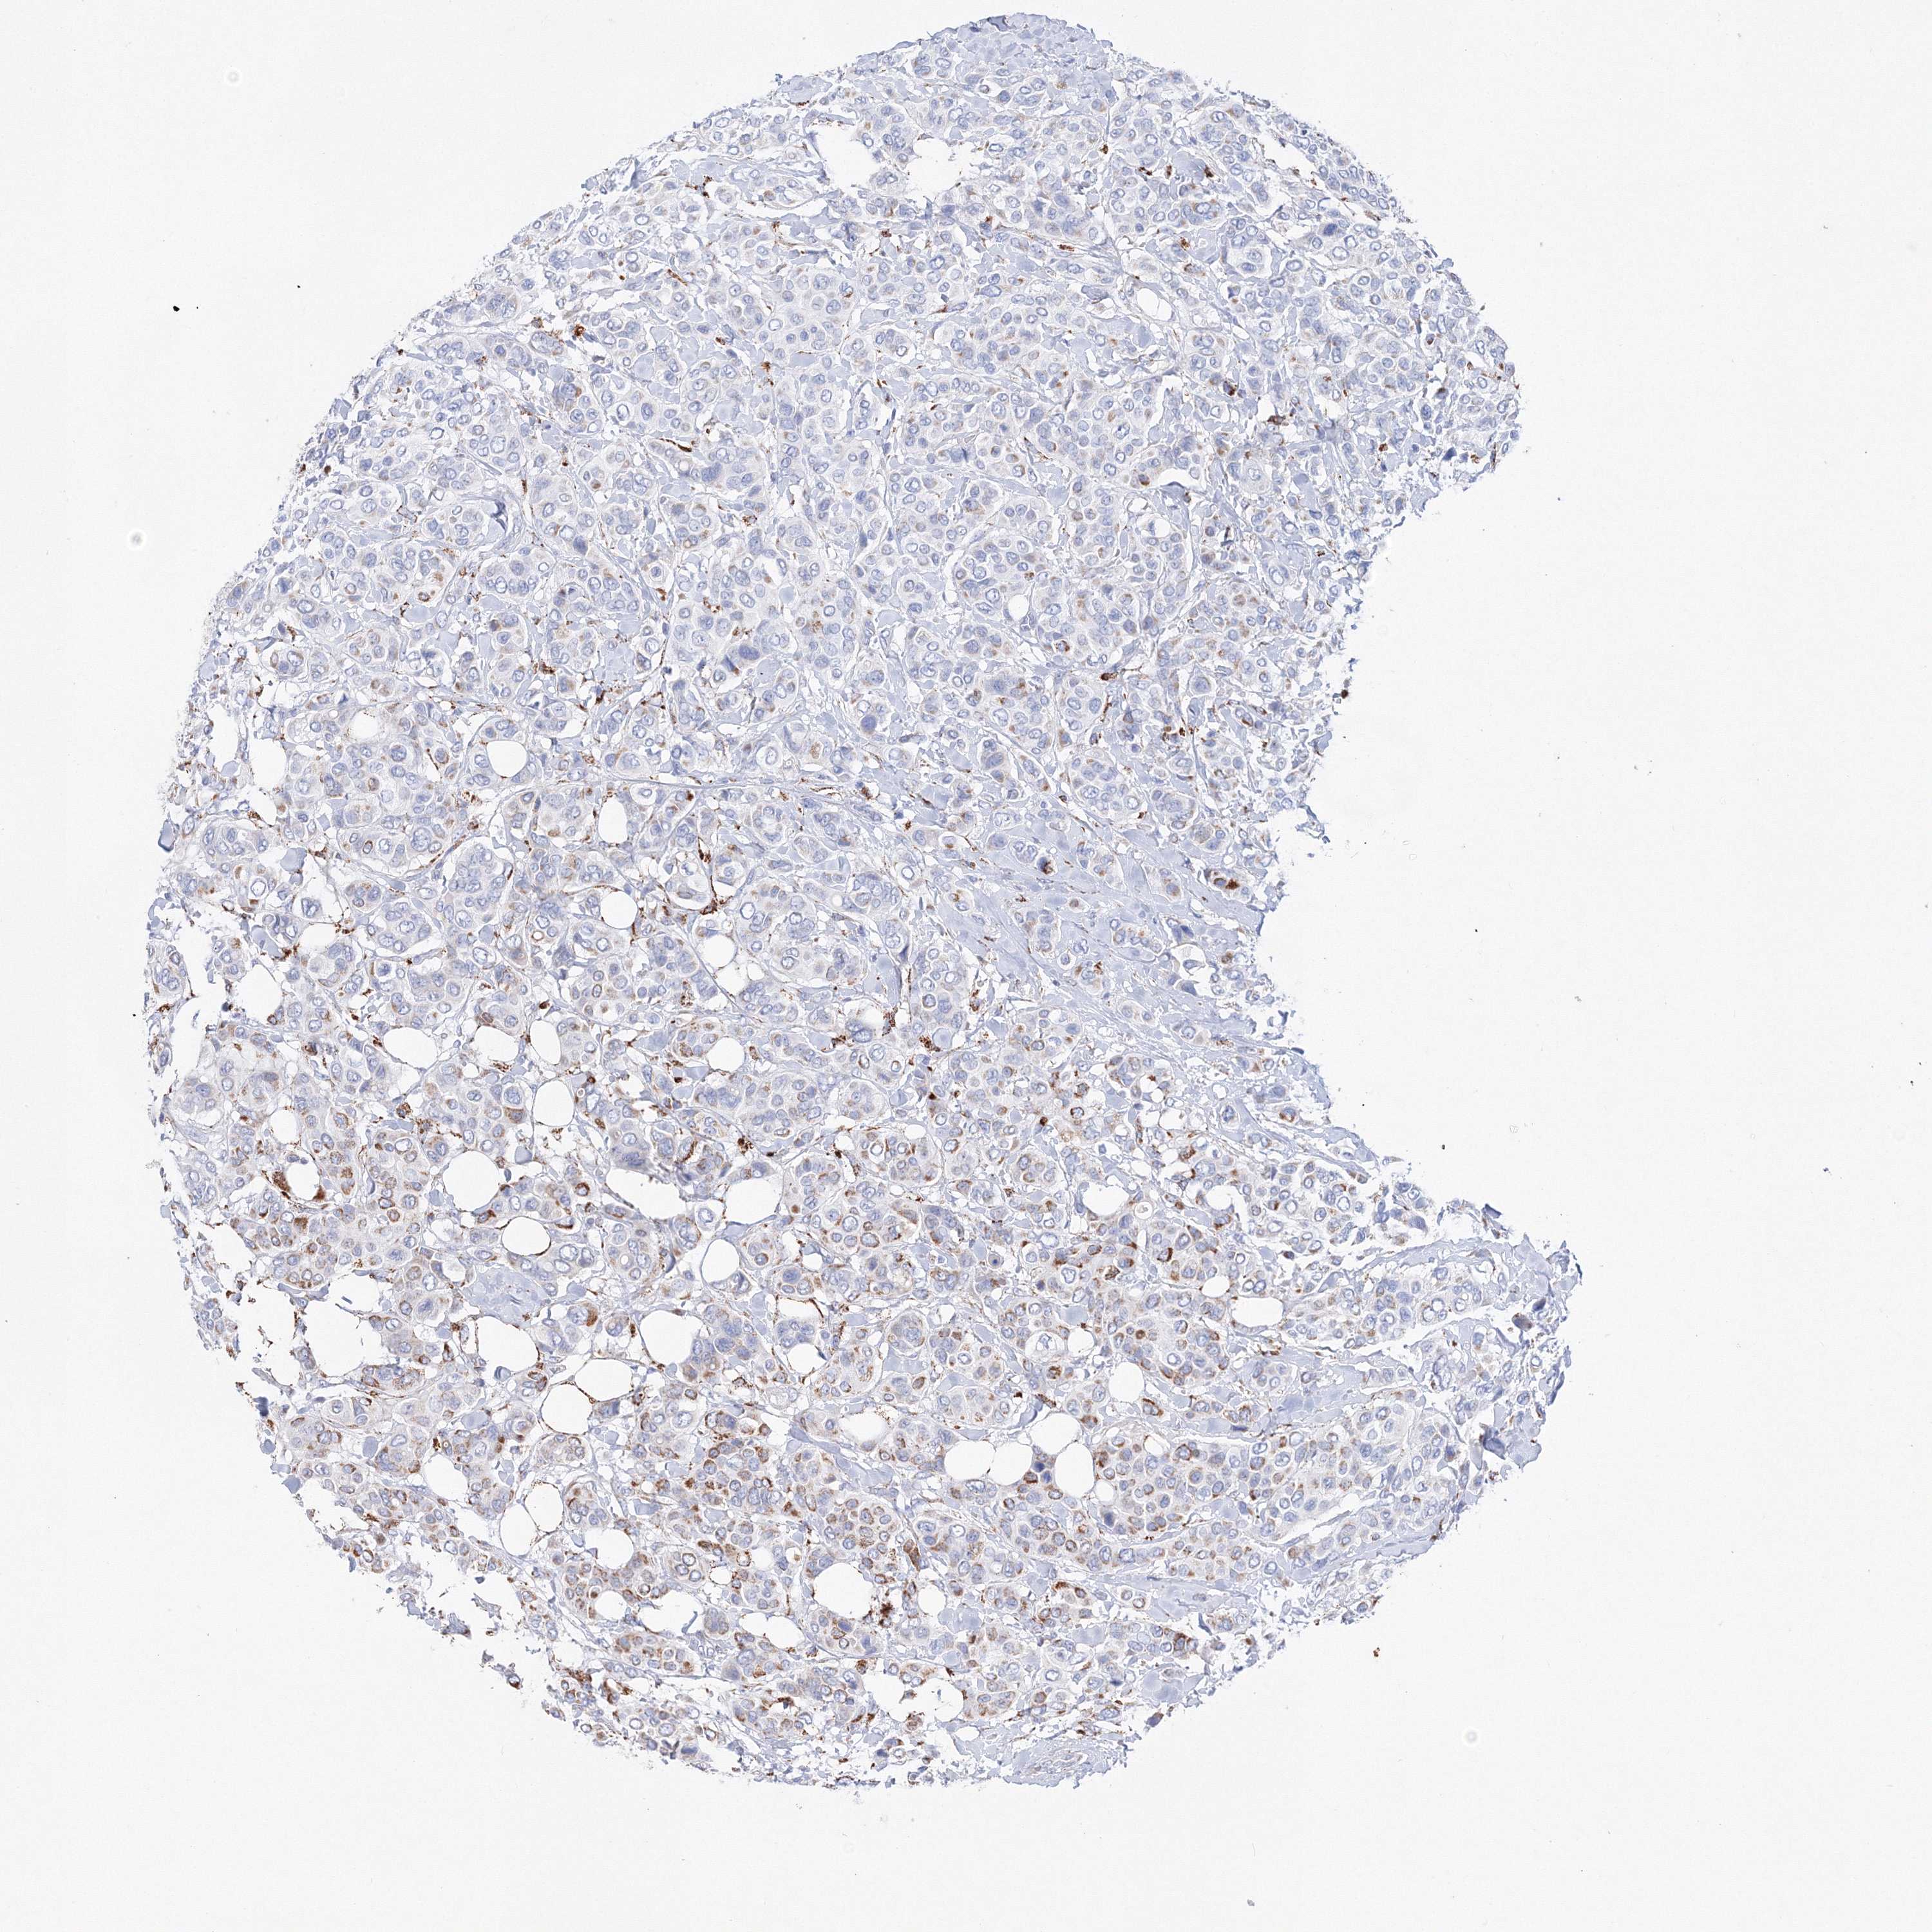

CANCER BREAST CANCER Show tissue menu

BRCA TCGA BRCA VALIDATION PROTEIN EXPRESSION